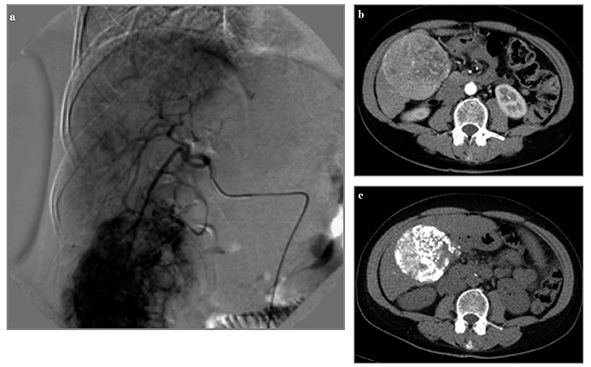

În ultimii ani a fost introdus un nou concept de TACE, cu microparticule încărcate cu medicamente citotoxice administrate intraarterial, care eliberează lent, la nivelul nodulului tumoral, citostaticul (TACE-DEBDOX – transarterial chemoembolization-drug eluting beads-doxorubicine). Aceasta tehnologie combină eficient administrarea locală a medicamentelor cu efectele embolizării. Studiile clinice efectuate au demonstrat necroza locală intensă și efectele secundare toxice sistemice mult reduse comparativ cu TACE clasic (fig. 2).

VM 25, p.12-13 - 2

Figura 2. a) Examinare IRM cu evidenţierea unui macronodul tumoral de cca. 5 cm, cu semiologie RM sugestivă pentru CHC; b) Angiografie hepatică cu evidenţierea unui nodul tumoral în segmentul VIII; c) evaluare IRM cu contrast specific hepatocitar, cu evidenţierea unui răspuns excelent la tratament cu reducerea dimensională importantă a nodulului tratat, cu răspuns complet.